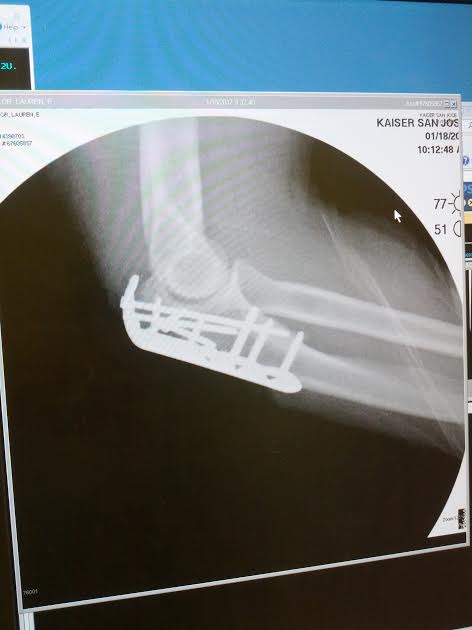

“I knew something was unusual, because my arm hurt more than it should. I’ve taken plenty of spills, but I was like ooooh, this really aches!” A good Samaritan helped her retrieve her bike and some nearby police came over. They put a safety cone in the pot hole to make sure nobody else hit it. And Sailor was off to the hospital. On Jan. 18 she had surgery and had a titanium plate and screws put into her arm.